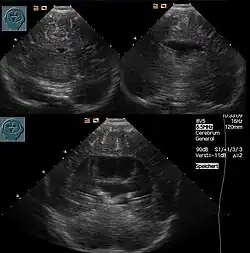

Die Diagnose kann vorgeburtlich im Rahmen von Pränataldiagnostik durch insbesondere Feinultraschalluntersuchungen im zweiten Trimenon, teils aber auch schon früher, gestellt werden. Während die Feststellung der alobären und der semilobären Form oft recht einfach ist, ist die der lobären Holoprosencephalie komplizierter.

Nachgeburtlich sind die Schnittbildverfahren Sonographie und Magnetresonanztomographie Methoden der Wahl.[19]